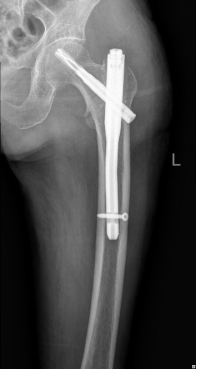

90岁的刘大爷,在洗澡时不小心滑倒至右侧“胯胯骨”痛,伴活动困难,由家属送至我院行X线片检查后诊断“股骨粗隆间粉碎性骨折”。大爷同时合并高血压、糖尿病、慢阻肺等多种基础疾病。入院后完善相关辅助检查,经过纠正贫血、电解质紊乱、调整血压血糖等积极处理,排除了绝对手术禁忌,在麻醉科、骨科团队的共同努力下成功为刘大爷实施了“股骨骨折闭合复位PFNA内固定术”,术中出血仅50ml,术后复查X片时骨折对位对线好,内固定可靠。在骨科医师及护理团队的尽心治疗及护理下,大爷恢复良好,术后5天可在助行器辅助下下地行走,术后2周正常出院。

针对老年髋部骨折,目前的治疗原则是尽早手术,尽早让患者离床活动,可使护理更加方便,减少呼吸系统、泌尿系统感染及压疮等并发症的发生,从而降低死亡率和减少髋内翻畸形的发生率。因此,对于伤前能够独立行走且无手术禁忌症的患者,推荐尽早进行手术,目前常用的手术方式包括闭合复位髓内钉内固定、关节置换、外固定架固定等。对于伤前不能行走的患者、疾病晚期患者及内科情况不能耐受手术的患者等,只能采取保守治疗。保守治疗需患肢牵引制动(时长约8-12周),牵引过程中需加强护理(定时翻身、踝泵运动等),预防相关卧床并发症。